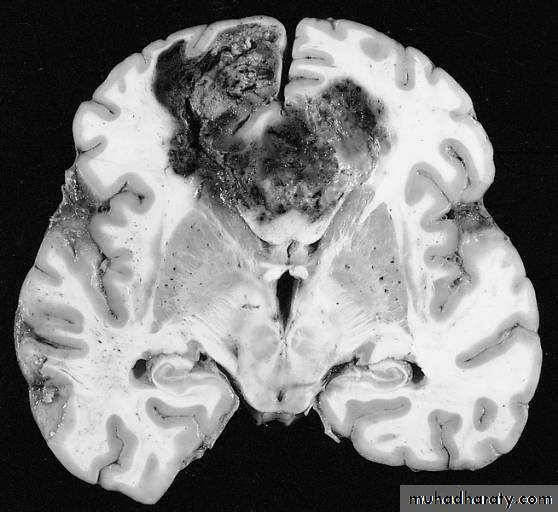

Glioblastoma multiformis:

The most malignant brain tumor, rapidly growing , red in color, highly vascular mainly affecting the cerebrum , some pathologists classify it as astrocytoma grade IV.Medulloblastoma:

( CORONAL MRI )